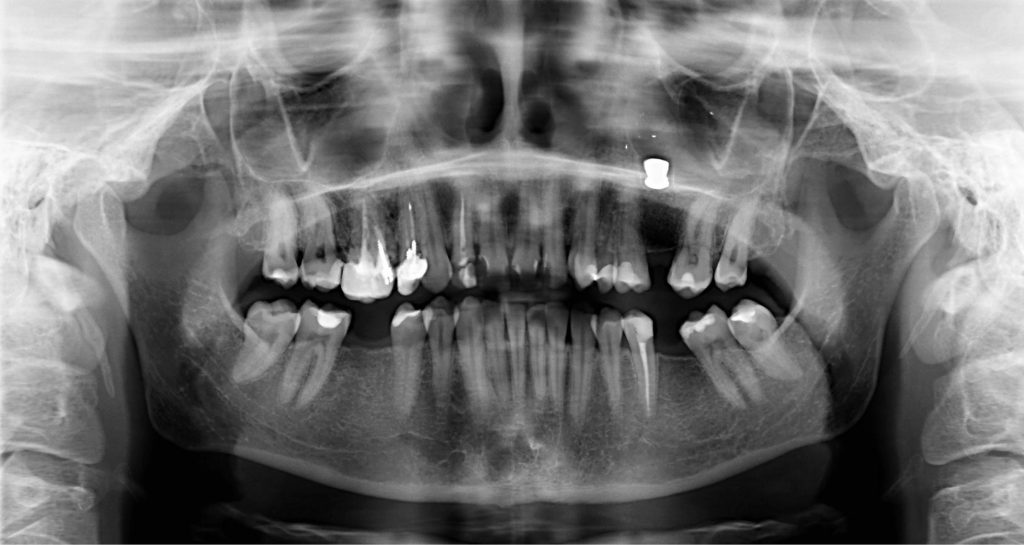

Streszczenie: Celem pracy jest przedstawienie przypadku 40-letniej pacjentki z ciałem obcym (śrutem) w zatoce szczękowej lewej zdiagnozowanym przypadkowo po wykonaniu zdjęcia panoramicznego zębów.

Summary: The aim of the paper is to present a case of a 40-year-old patient with a foreign body (buckshot) located in the maxillary sinus, accidentally diagnosed during panoramic dental X-ray examination.